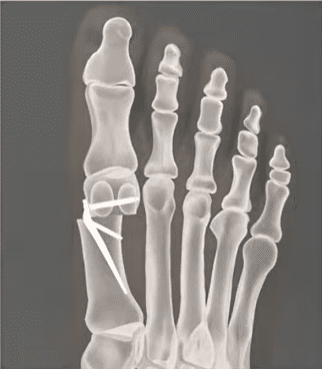

butyok mutet elott

butyok mutet utan